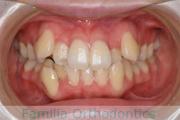

No.20V-496

- 叢生

- 年齢:

- 15歳

- 性別:

- 女性

- 抜歯部位

- 上:

- 84|58

- 下:

- 8558

全体的なでこぼこを治したいということで来院されました。上顎は右は4,左と下顎両側は5番を抜歯して、マルチブラケット法にて治療を行いました。2年強、25回程度の通院をしていただきました。

非常に強いでこぼこですので、後戻りのリスクは高めであると思われます。

- ≫治療後

-

上顎

下顎

前歯の関係など

右側

正面

左側